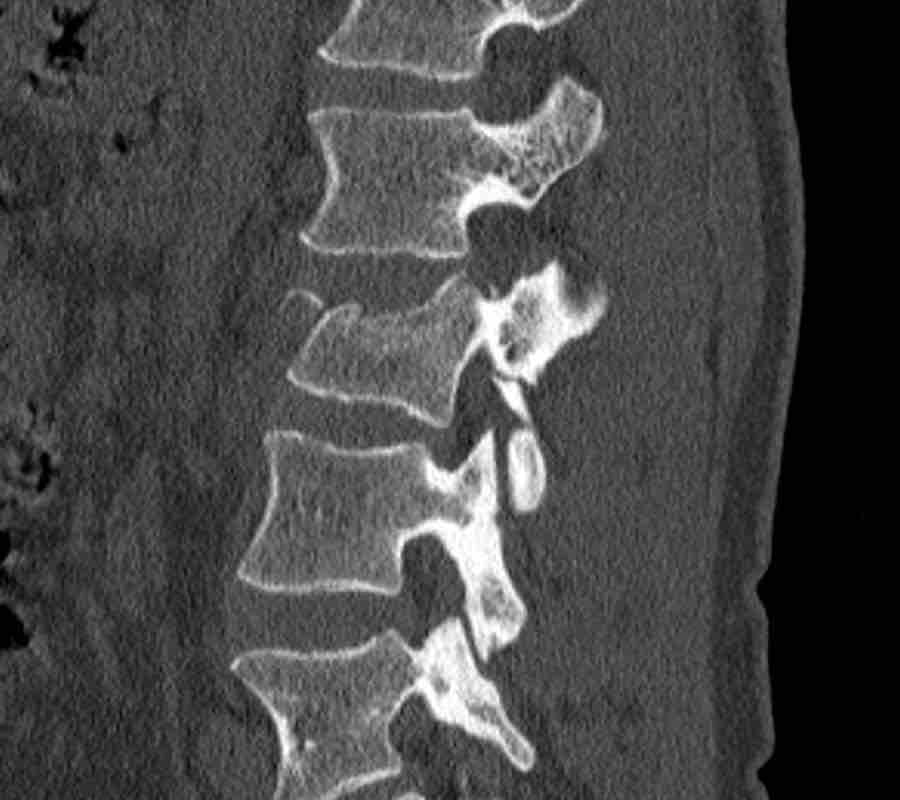

Scroll through the images.

What is the highest AO-type of injury?

Any additional findings?

Then continue with the next images…

Findings

- Black arrows: horizontal fractures through the pedicles as a result of flexion distraction trauma.

- White arrows: soft tissue swelling indicating injury to posterior ligaments.

- Circle: compression fracture of posterior wall (2 points) and two endplates (2 points)

Conclusion

Type B2-A4

Flexion distraction injury with separation on the posterior side and a secondary burst fracture involving both endplates and the posterior wall.